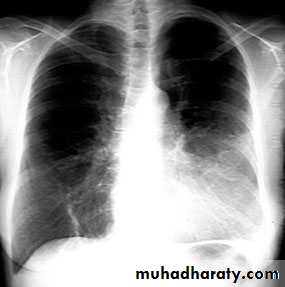

NORMAL PA view